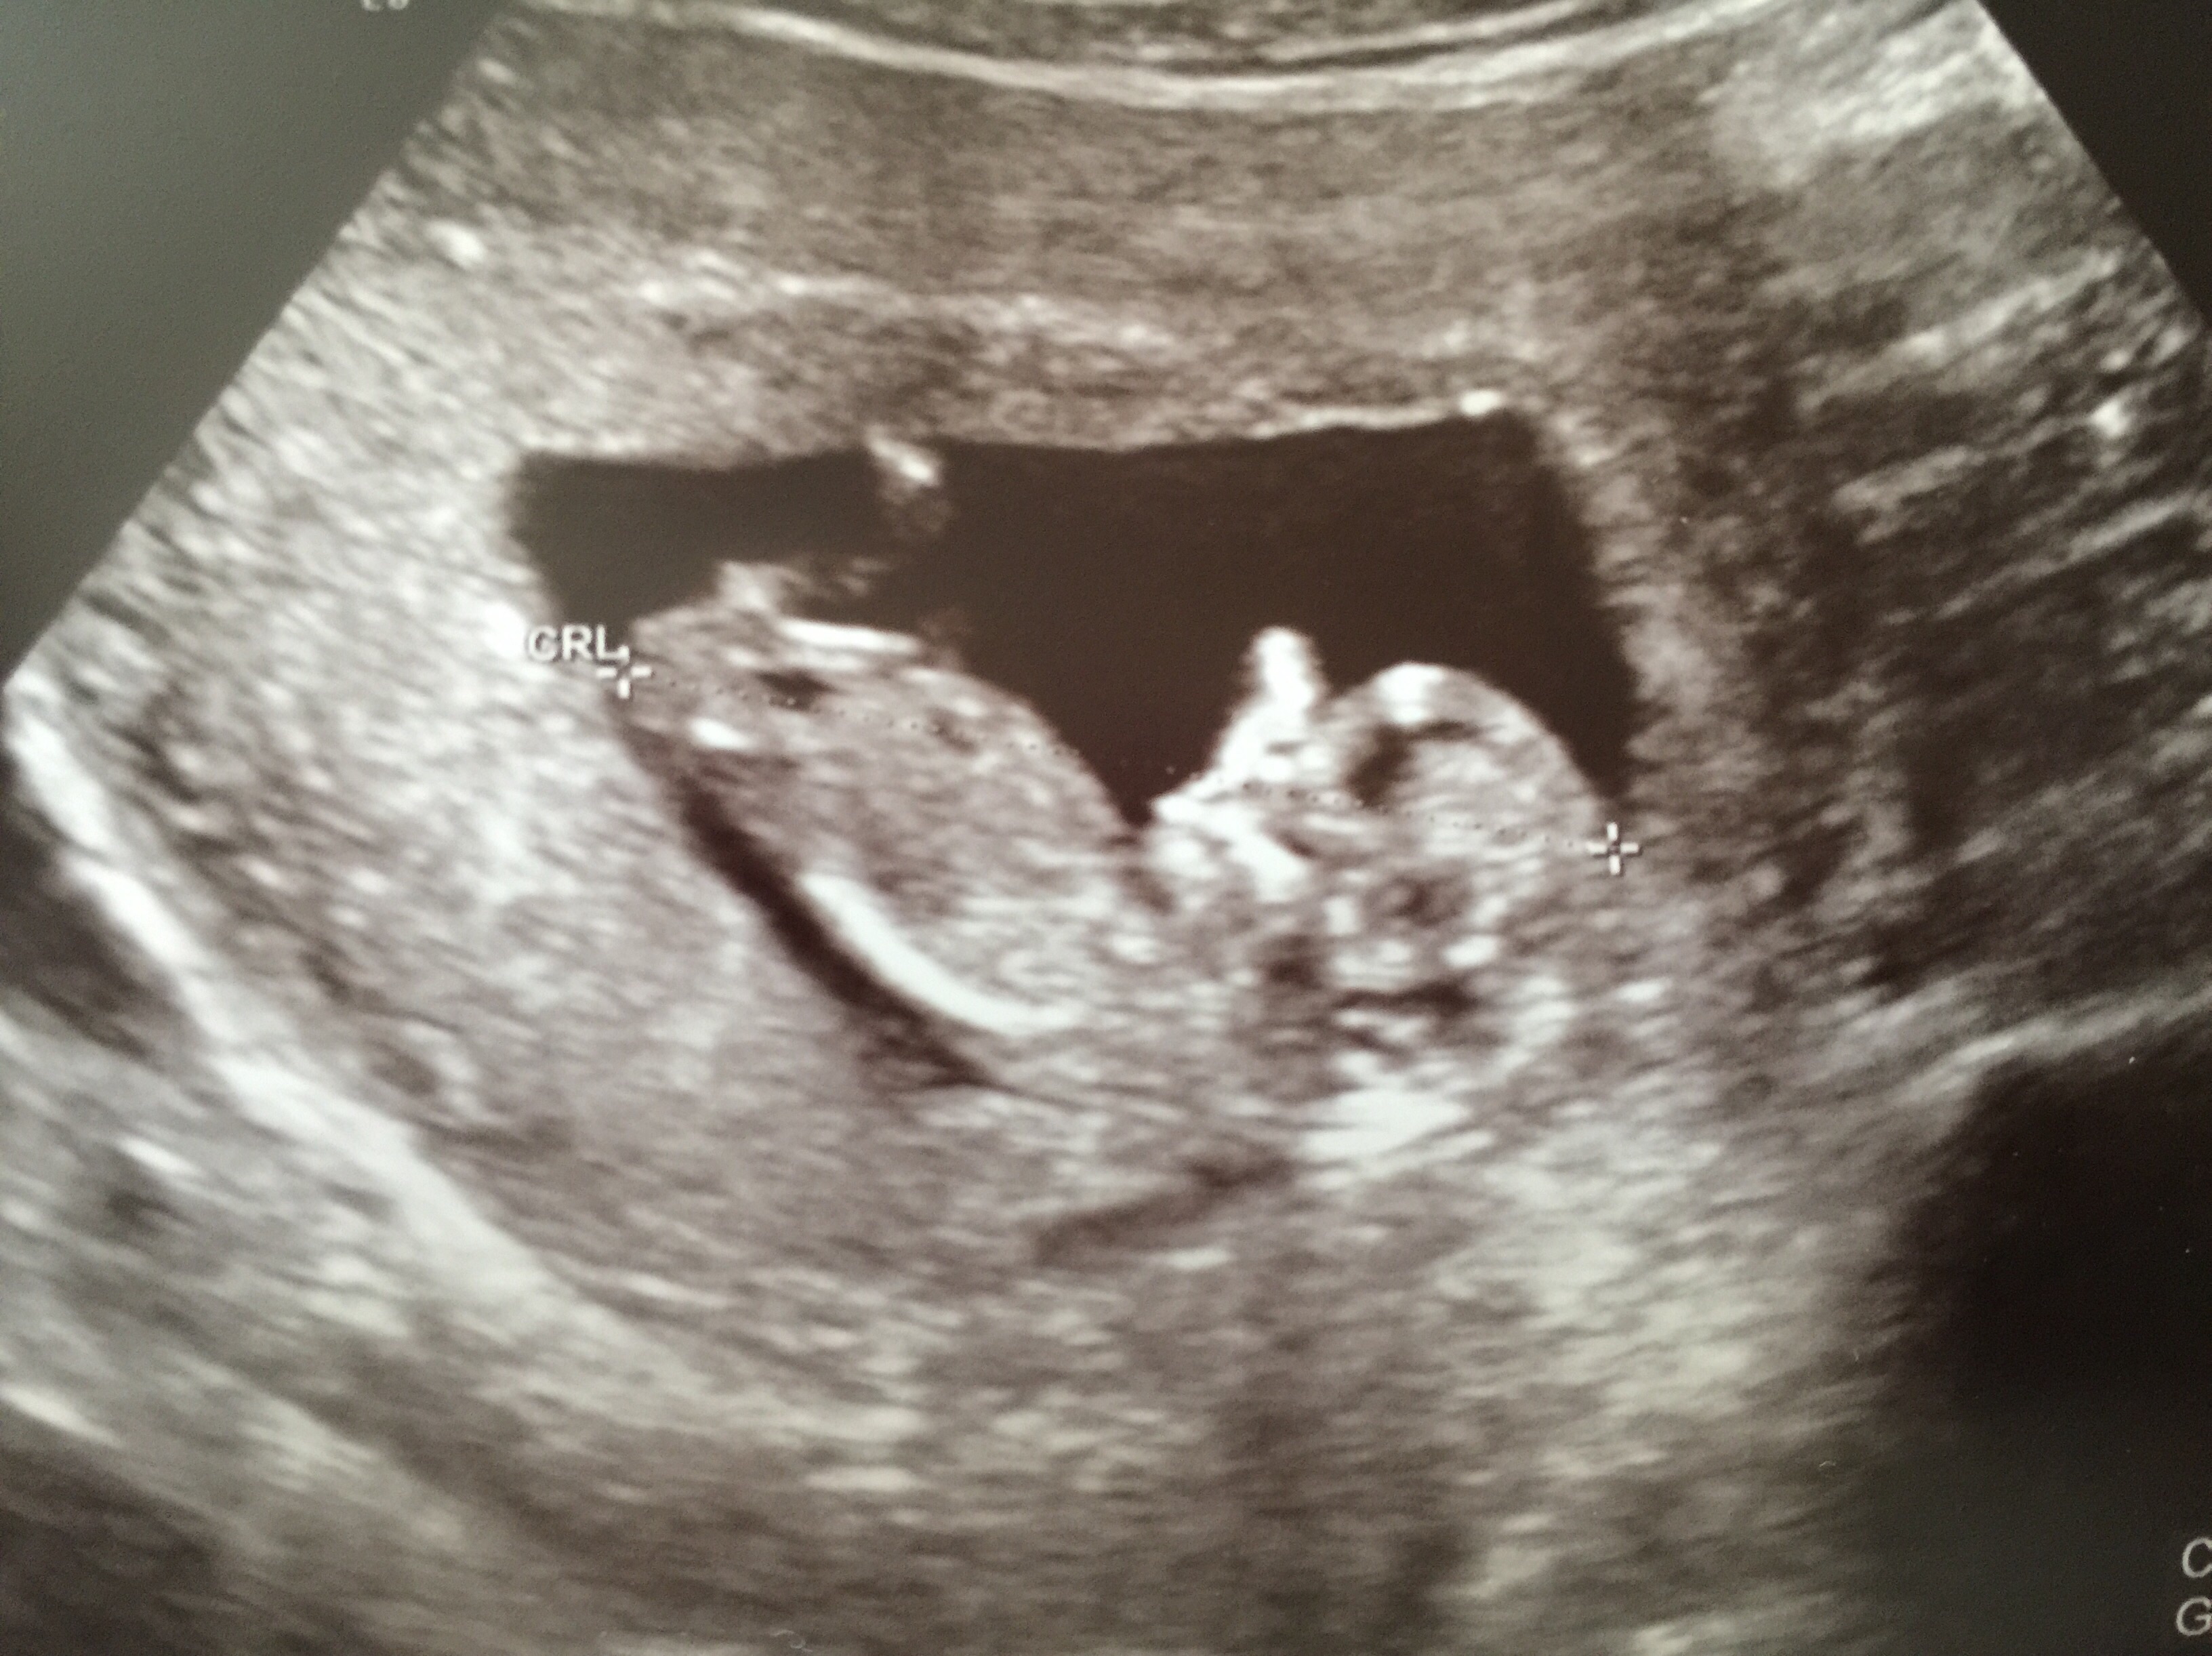

This ultrasound was done at 9w 3d. 12w 1d today . Wish I would have had one done a little further along to see something more . Fhr at 173 bpm. This is baby #2 we're really stoked

12w 1d today . Wish I would have had one done a little further along to see something more . Fhr at 173 bpm. This is baby #2 we're really stoked